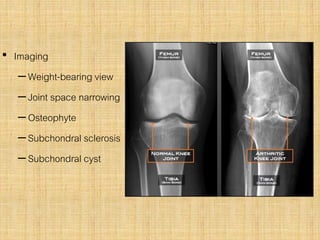

• Imaging

–Weight-bearing view

–Joint space narrowing

–Osteophyte

–Subchondral sclerosis

–Subchondral cyst

• Imaging –Weight-bearing view –Jointspace narrowing –Osteophyte –Subchondral sclerosis –Subchondral cyst